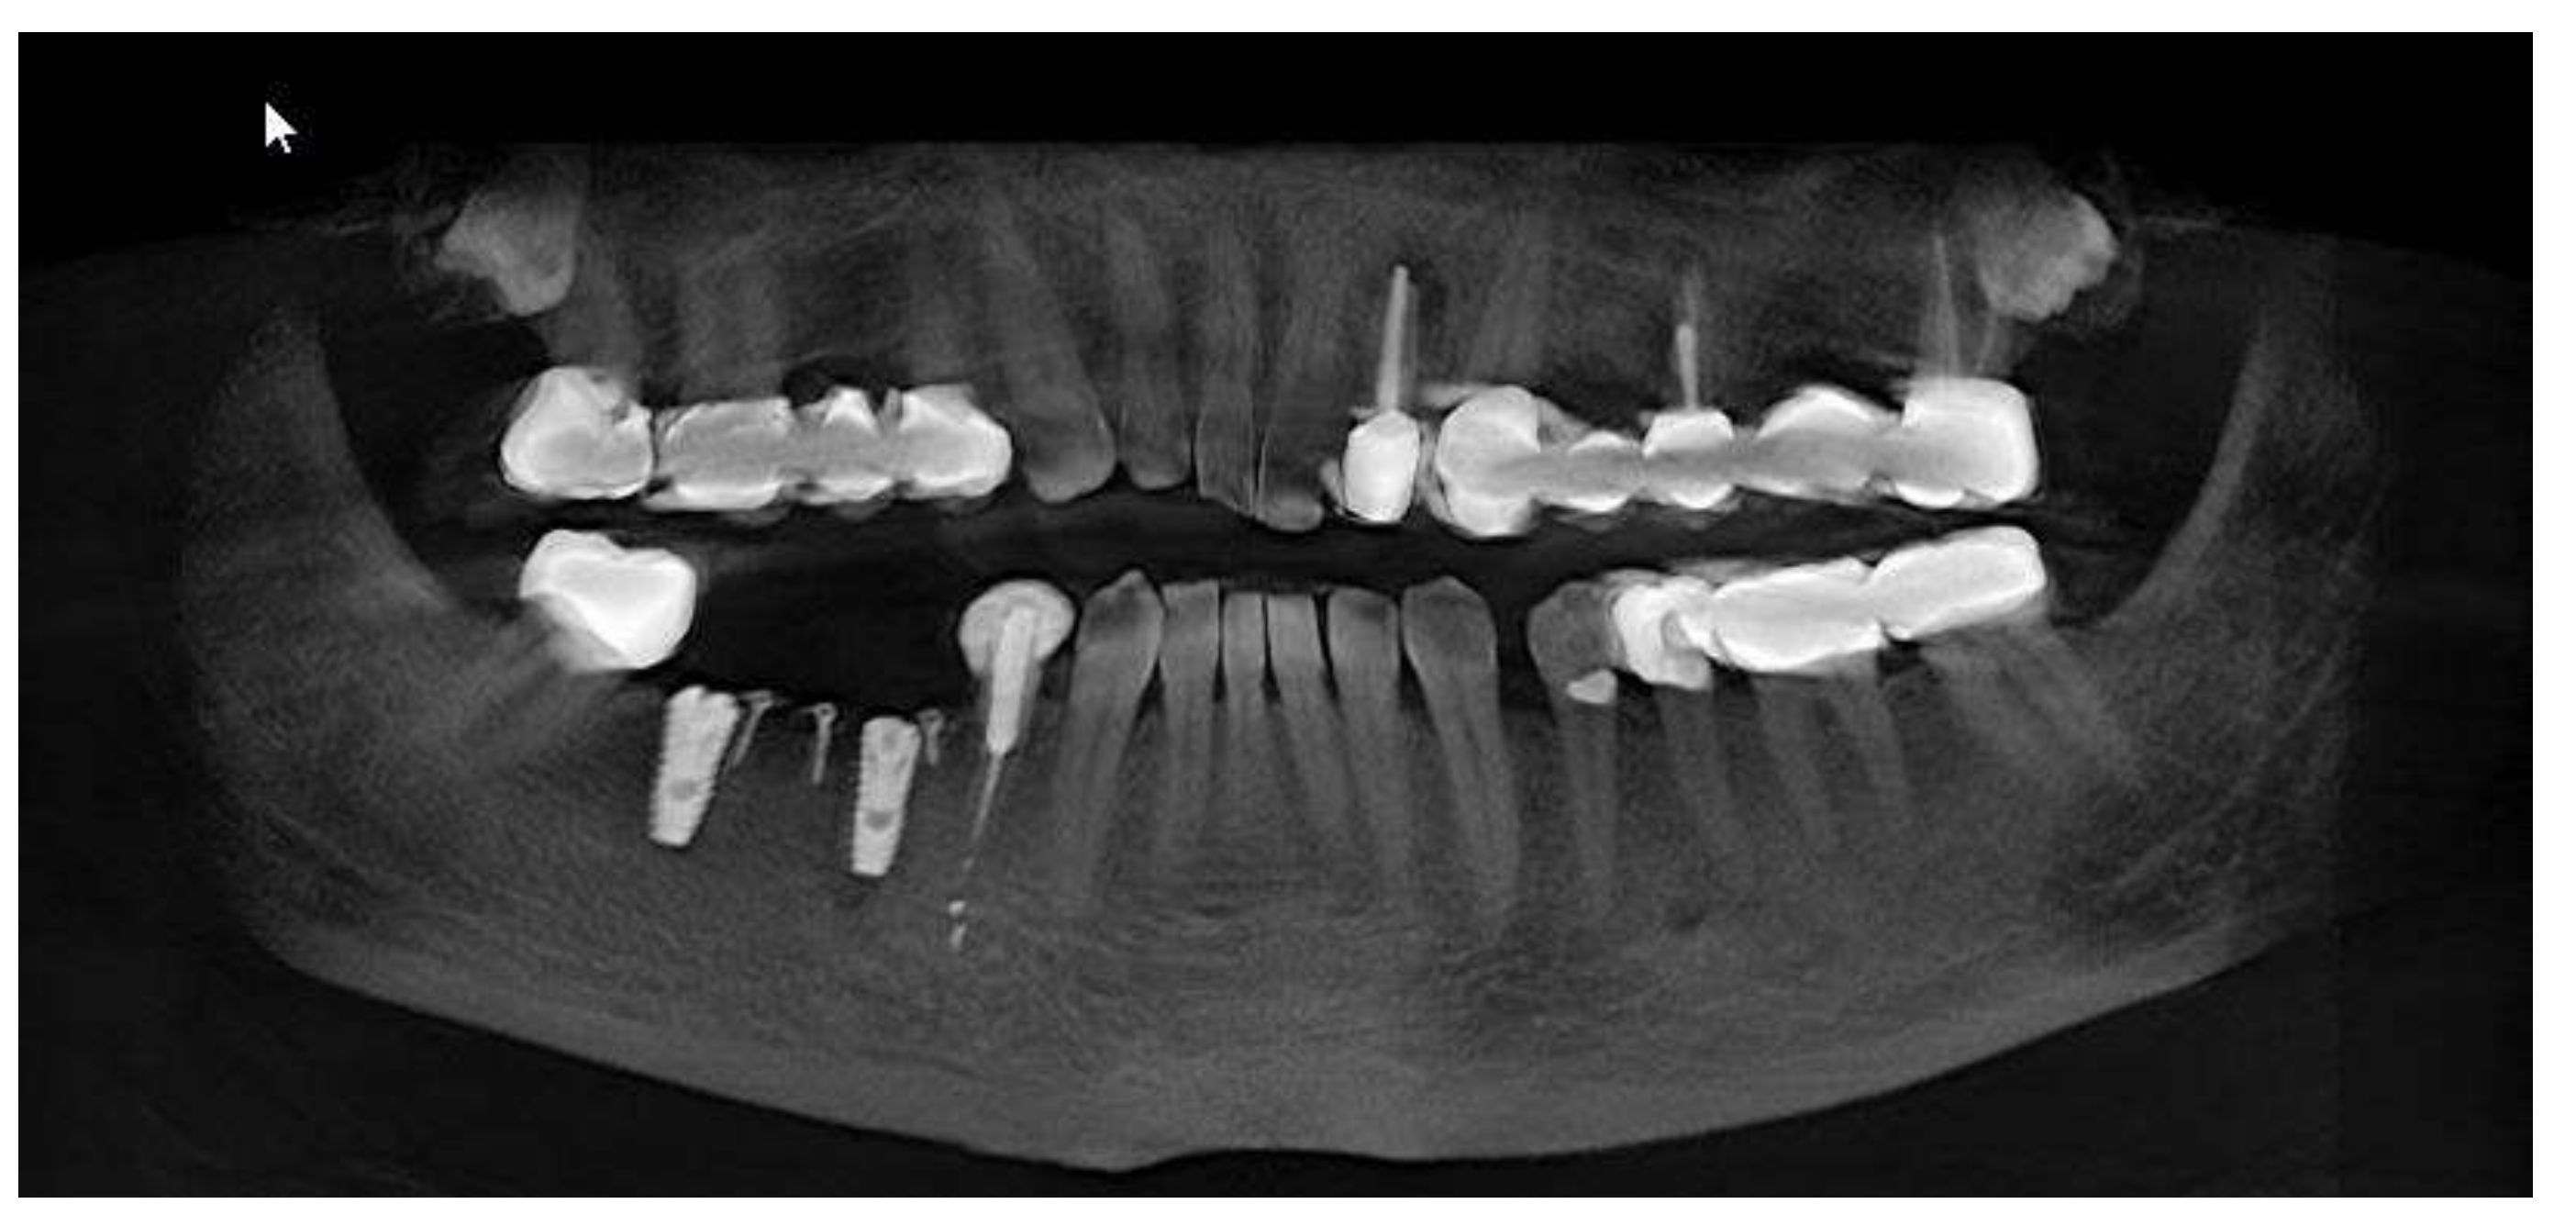

Clinical and CBCT aspects of patient from the test group, describing the stages of S-GBR technique and implant-prosthetic stage, are presented in Figure 1, Figure 2, Figure 3, Figure 4, Figure 5, Figure 6, Figure 7, Figure 8, Figure 9, Figure 10 and Figure 11. CBCT exam allows the evaluation of the horizontal alveolar bone defect and the position of the mandibular alveolar nerf (Figure 1A,B). Figure 1C,D show cross-sectional CBCT aspects of the implant sites. Figure 2 shows the narrowed mandibular alveolar bone with horizontal resorption. Figure 3 shows the exposed buccal surface of the alveolar ridge with severe horizontal resorption, after flap opening. The inserted implants (4.5 mm diameter, 11.5 mm length) and osteosynthesis screws (45° from the occlusal plan) are shown in Figure 4A. The placement of graft (autologous bone and xenograft) and collagen membrane is shown in Figure 4B. Figure 5A shows tension-free sutures, due to periosteal incisions alveolar ridge. Figure 5B shows clinical aspect at 7 months after surgery, with gingival tissue adherent on the reconstructed alveolar ridge. Figure 6 shows OPG aspect at follow-up of 7 months, with osseointegration of the dental implants. Figure 7A shows clinical aspect before osteosynthesis screws removal. Figure 7B shows clinical aspect after osteosynthesis screws removal. Figure 8A shows healthy peri-implant soft tissues. Figure 8B shows repositioning key for perfect position of abutments. Figure 10A,B show clinical aspects of implant-supported prosthetic restoration. Figure 11A,B show CBCT aspects of Osseo integrated dental implants at 24 months follow-up.

Figure 6.

OPG aspect at follow-up of 7-months.